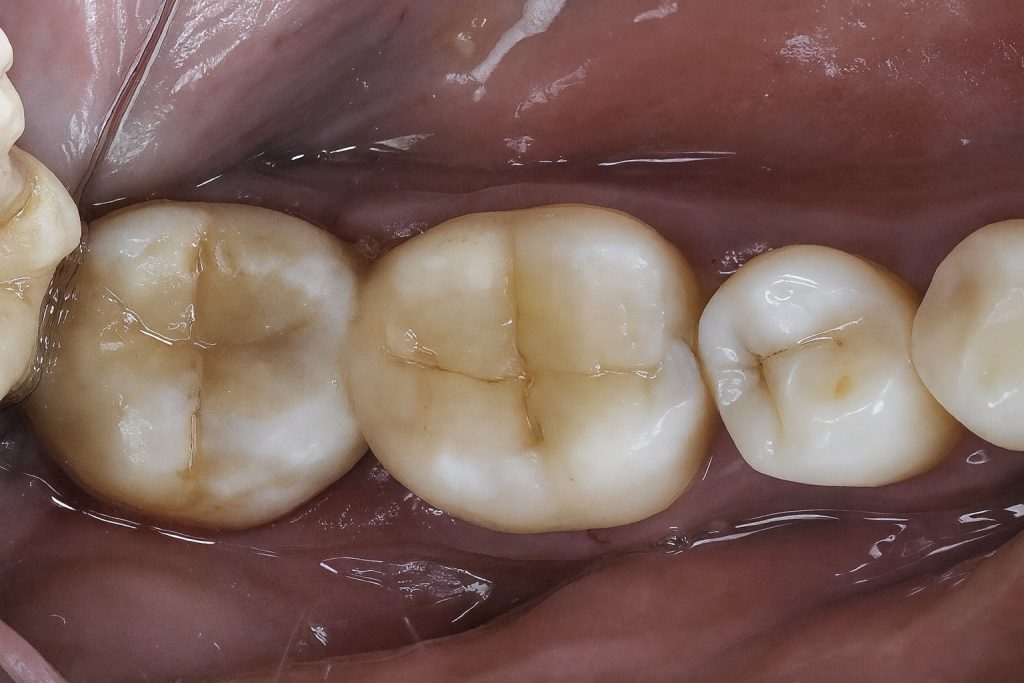

This case demonstrates the management of proximal caries in posterior teeth using direct composite restorations with proper isolation and sectional matrix technique. The goal was to achieve functional occlusion, tight proximal contacts, and seamless esthetics through minimally invasive adhesive dentistry.

8. Final Result